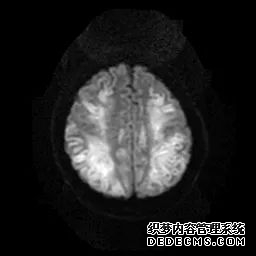

脑MRI显示尾状核、扁豆状核和脑梗头部T2/FLAIR呈双侧对称异常高信号。扩散限制涉及这些区域,其特征是扩散加权DWI(B-1000)上的高强度,ADC图上相应的减弱强度。

印象:通过将这些成像模式与临床和实验室检查结果相结合,就有可能得出低血糖性脑病。

影像影响内囊后肢、大脑皮层(特别是枕叶和岛叶)、海马和基底节区,常是双边对称性的。